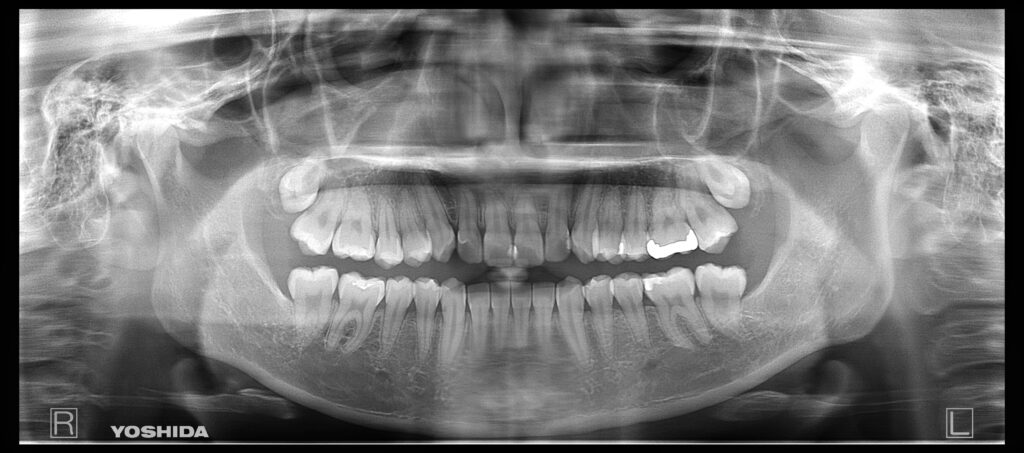

①親知らず抜歯後